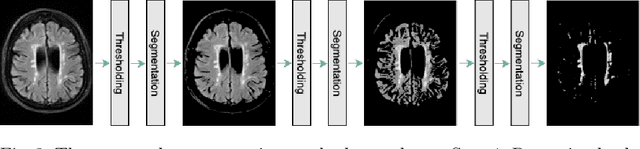

Abstract:In real-world clinical settings, traditional deep learning-based classification methods struggle with diagnosing newly introduced disease types because they require samples from all disease classes for offline training. Class incremental learning offers a promising solution by adapting a deep network trained on specific disease classes to handle new diseases. However, catastrophic forgetting occurs, decreasing the performance of earlier classes when adapting the model to new data. Prior proposed methodologies to overcome this require perpetual storage of previous samples, posing potential practical concerns regarding privacy and storage regulations in healthcare. To this end, we propose a novel data-free class incremental learning framework that utilizes data synthesis on learned classes instead of data storage from previous classes. Our key contributions include acquiring synthetic data known as Continual Class-Specific Impression (CCSI) for previously inaccessible trained classes and presenting a methodology to effectively utilize this data for updating networks when introducing new classes. We obtain CCSI by employing data inversion over gradients of the trained classification model on previous classes starting from the mean image of each class inspired by common landmarks shared among medical images and utilizing continual normalization layers statistics as a regularizer in this pixel-wise optimization process. Subsequently, we update the network by combining the synthesized data with new class data and incorporate several losses, including an intra-domain contrastive loss to generalize the deep network trained on the synthesized data to real data, a margin loss to increase separation among previous classes and new ones, and a cosine-normalized cross-entropy loss to alleviate the adverse effects of imbalanced distributions in training data.